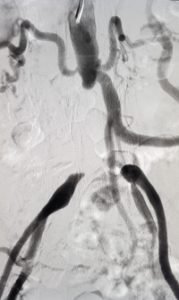

CT Angiography

CT Angiography (CT guided non-invasive angiography) is a highly confirmatory test and helps in exact treatment and management plan. By this test, we can evaluate the exact site, extent, and type of blockages, as well as the size of blood vessels (we can decide whether blockages can be treated by angioplasty or will require a peripheral bypass). This provides a road map which helps us keep planning further treatment.